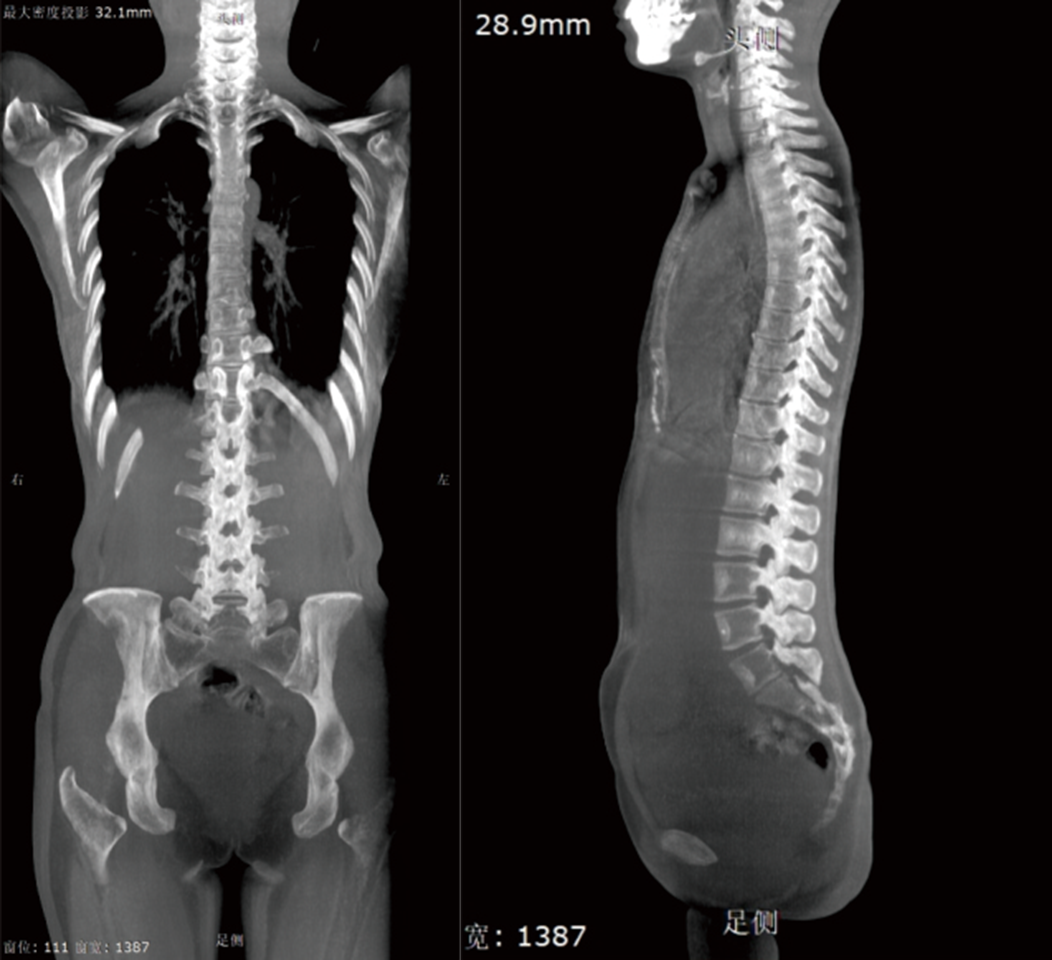

MIP (Projektion mit maximaler Intensität)

Die maximale Intensitätsprojektion kann die Gesamtsituation der gesamten Wirbelsäule des Patienten deutlich widerspiegeln.